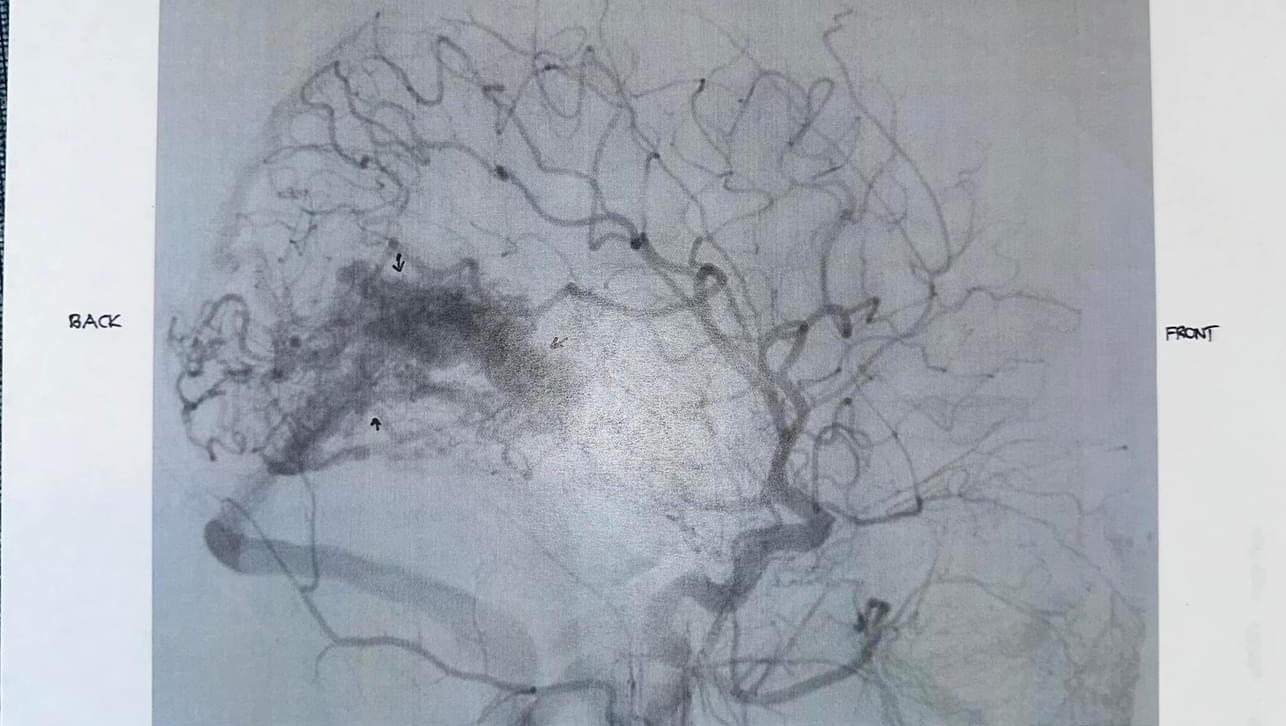

Early in December, she began complaining of a severe headache. Headaches are nothing new for Kenzie. She has had intermittent migraines with “visual auras”over the last several years. But after 9 days of failed outpatient treatment, we headed to the ER, where an MRI revealed a large (grade 4) Occipital AVM.

AVMs or Arteriosclerosis-Venous Malformations are an area of blood vessels that, instead of forming in straight lines, form in a bundle (or, as Kenzie likes to say, a knot). Instead of having clear high-pressure tolerant arteries and low pressure venous drainage, these vessels are mismatched and hopelessly tangled. Because of this malformation, there is also no capillary bed within her “knot” to allow oxygen and nutrient to exchange. AVMs are the leading cause of stroke in the pediatric population and are often not discovered unless one of those vessels ruptures and bleeds.

We were quickly transferred to OHSU and placed in the amazing care of their neurosurgical team for ongoing testing. This included a brain angiogram and that showed her AVM was larger than originally thought, measuring about 5cm x 3cm. During that hospitalization, it was discovered that her AVM has already started to cause her permanent side effects. She has lost a good portion of her left upper field of vision in both eyes.